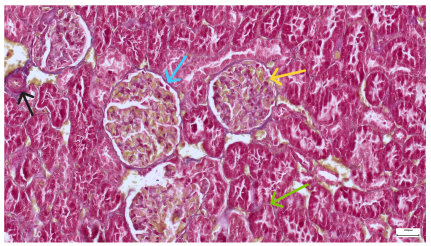

Table 4 below presents histological proof for renal damage in the G-IV group suffering from a dual metabolic impairment, albeit treated with statin.

Table 4.

Histological proof for renal damage in the diabetic-and-obese statin-treated group G-IV.

The histological extent of lesions suggests a definite inflammatory process in the renal matrix and glomeruli, but the extent of the disruptive process as resulting from an average nephron pool loss is limited. This is consistent with the limited duration of our experiment, with definite development of chronic kidney disease taking sometimes as long as 24 weeks. However, expecting this limited extent of damage, we chose a relatively short—proportionate—duration of statin treatment. Our results demonstrate a statistically significant higher retention of creatinine and urea in plasma—a reflection of the respective reduction in renal function—in every single experimental group (G-II to G-IV) in comparison to the control group G-I. The diabetic group G-III demonstrates the highest values for both creatinine and urea across the whole experiment population. The plasma concentrations of retention byproducts in both G-II and G-III are statistically significantly higher compared to the control G-I, indicating that each condition independently leads to important impairment in kidney function. The assumption of concurring actions in a model exhibiting obesity and diabetes simultaneously should translate into outcomes—renal and inflammatory—with values skewed from normality, the dimension of departure from the normal range at least as big as in any of the models exhibiting an individual condition.